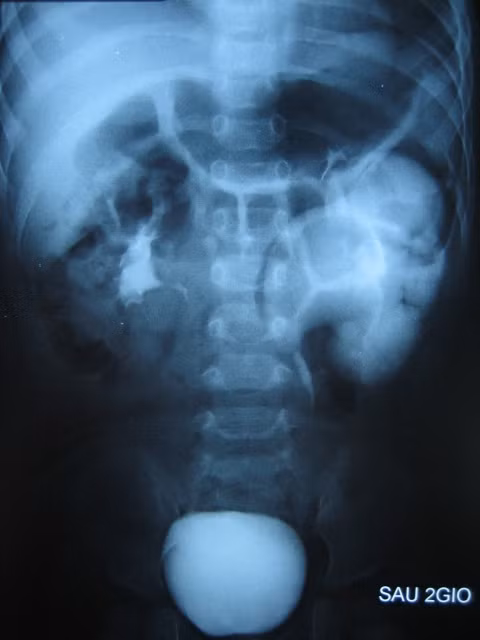

| Hình ảnh hai quả thận nhưng có chung 1 niệu quản của bé V. |

Bé A. được phẫu thuật tạo hình lại niệu quản mới, cắt bỏ đoạn hẹp giúp việc tháo xuất nước tiểu dễ dàng, hiện bé đang hồi phục và đã ăn uống lại bình thường. Dị tật bẩm sinh hai quả thận nhưng có chung một niệu quản, hay còn gọi Thận niệu quản đôi dạng “Y” vì hình thái chung niệu quản của hai quả thận giống như chữ Y. Dị tật bẩm sinh này rất hiếm gặp, tại bệnh viện Nhi đồng 2 trong vòng 10 năm chỉ gặp khoảng 3 trường hợp.

Theo ThS.BS Ngọc Thạch, do hình thái giải phẫu bất thường này mà dẫn đến những hệ lụy như nước tiểu của thận này chạy ngược vào thận kia gây nhiễm trùng tiểu cũng như sẹo thận về sau; bên cạnh đó phía thận nằm dưới cũng thường ứ nước hẹp niệu quản. Như trường hợp của bé A. các BS phải cắt bỏ đoạn niệu quản hẹp gây ứ nước và khâu nối với đoạn niệu quản lành giúp nước tiểu lưu thông tốt hơn.